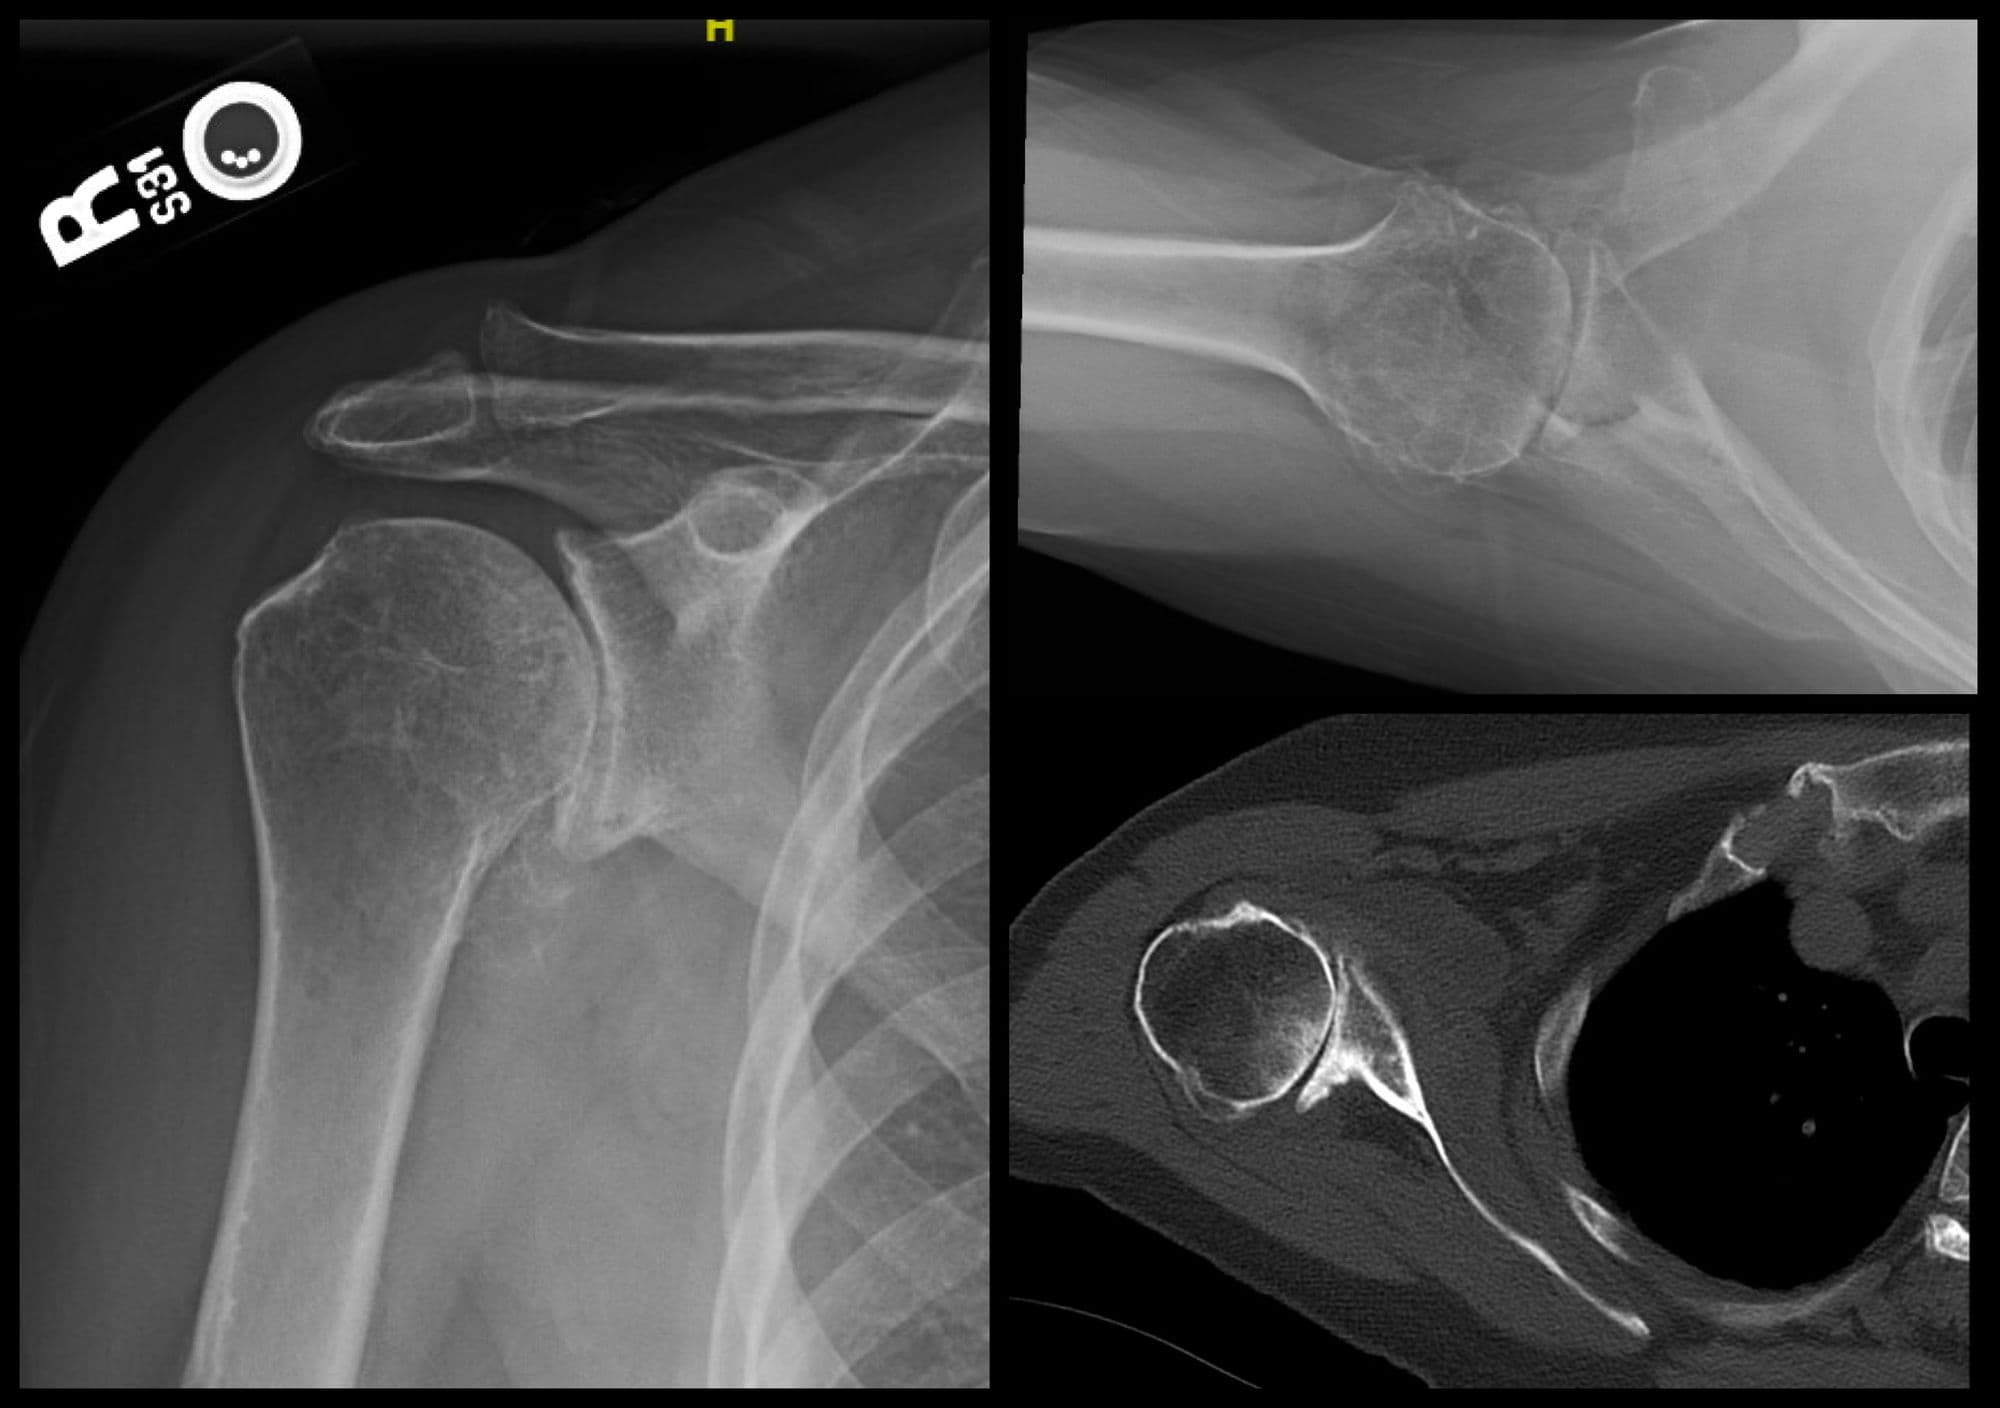

Glenoid Reconstruction with Allograft

Imaging

Pre-op